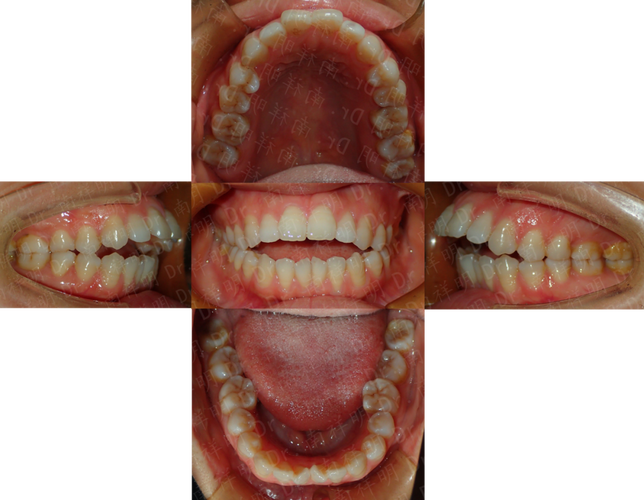

通常在PAOO手术前,正畸医生会进行短期的术前正畸,目的是排齐牙弓、建立初步的咬合关系,为手术创造更理想的条件,并确保术后牙齿能顺利移动到预定位置。